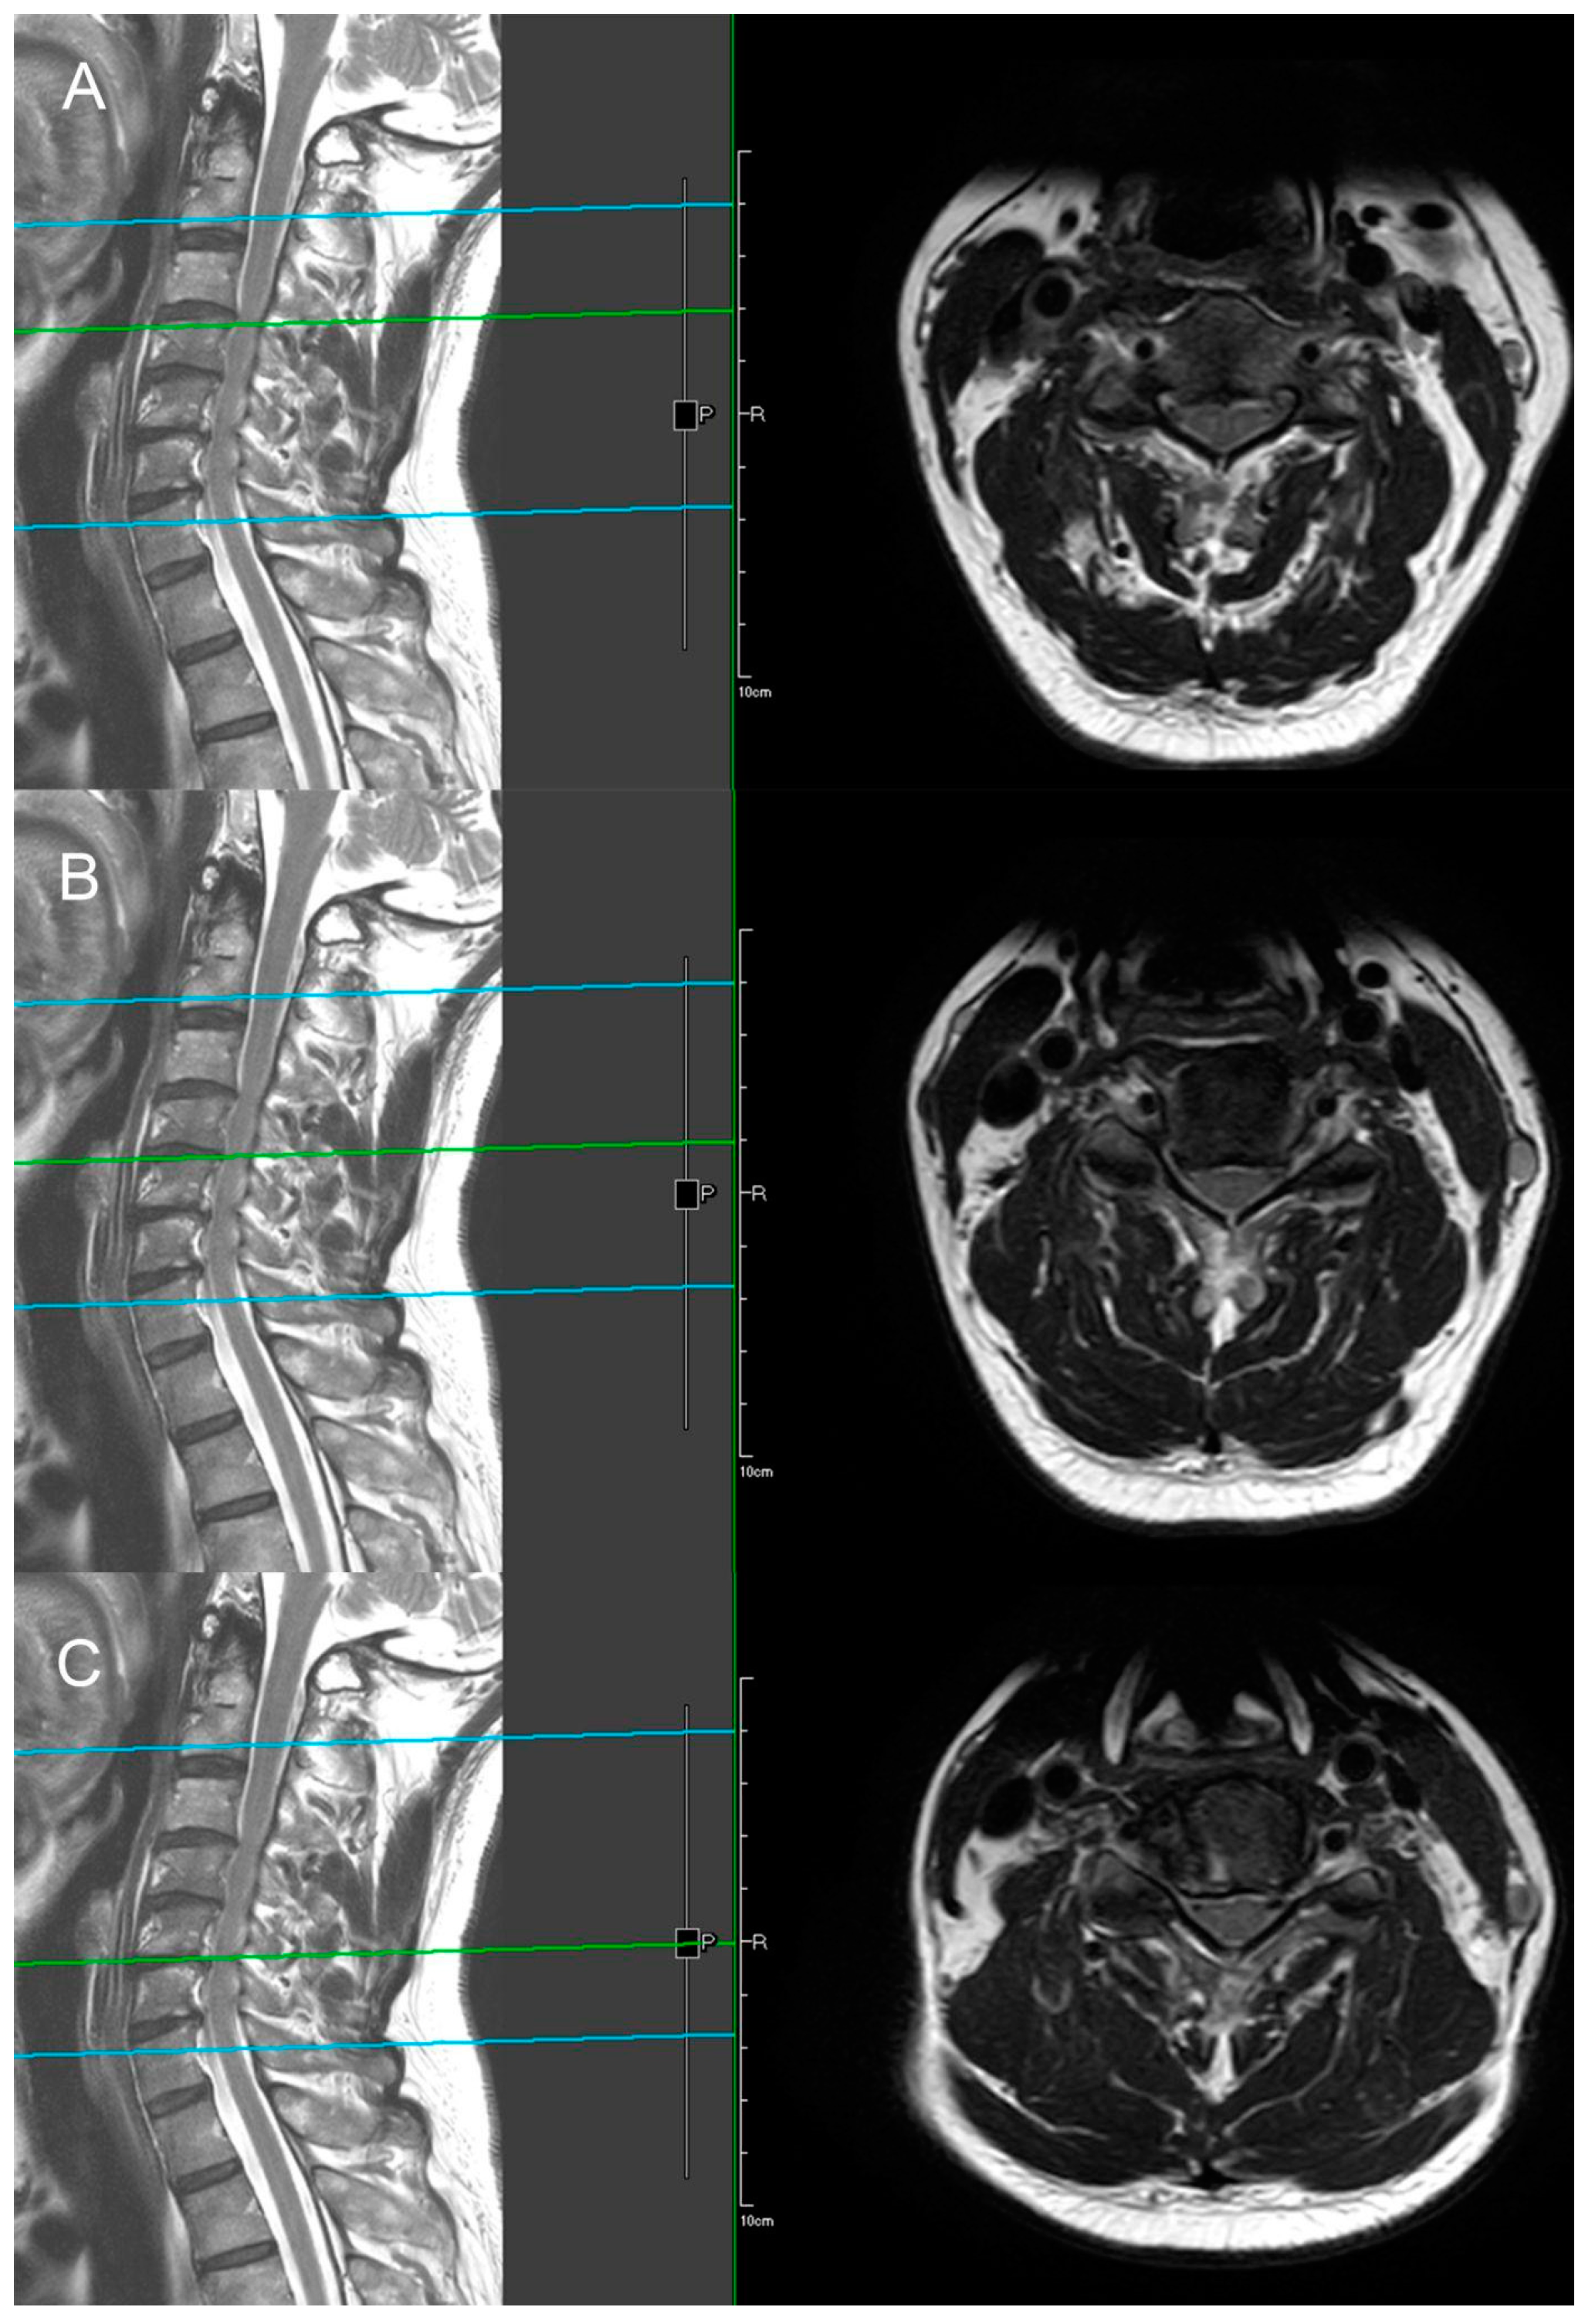

The X-ray demonstrates normal cervical lordosis and a positive K-line. There is evidence of bilateral foraminal spur formation at C3-6 and left foraminal spur formation at C6-7. MRI findings indicate C3-7 degenerative spondylosis with central spinal stenosis at C3-6, bilateral foraminal spur formation with stenosis at C3-6, more pronounced on the right side, and left foraminal spur formation with stenosis at C6-7. However, due to the relatively inconspicuous nature of left-sided radiculopathy, surgical intervention at the C6-7 segment was not pursued (Figure 8 and Figure 9). The patient’s preoperative modified Japanese Orthopaedic Association score was recorded as 16, and his visual analog scale neck pain was rated at 8.

Figure 9. MRI sagittal and axial views illustrating bilateral foraminal stenosis and central stenosis at the C3–C6 levels. ((A) C3–C4, (B) C4–C5, (C) C5–C6). In the left image, the green line represents the relative position of the axial plane MRI of the cervical spine shown in the right image.